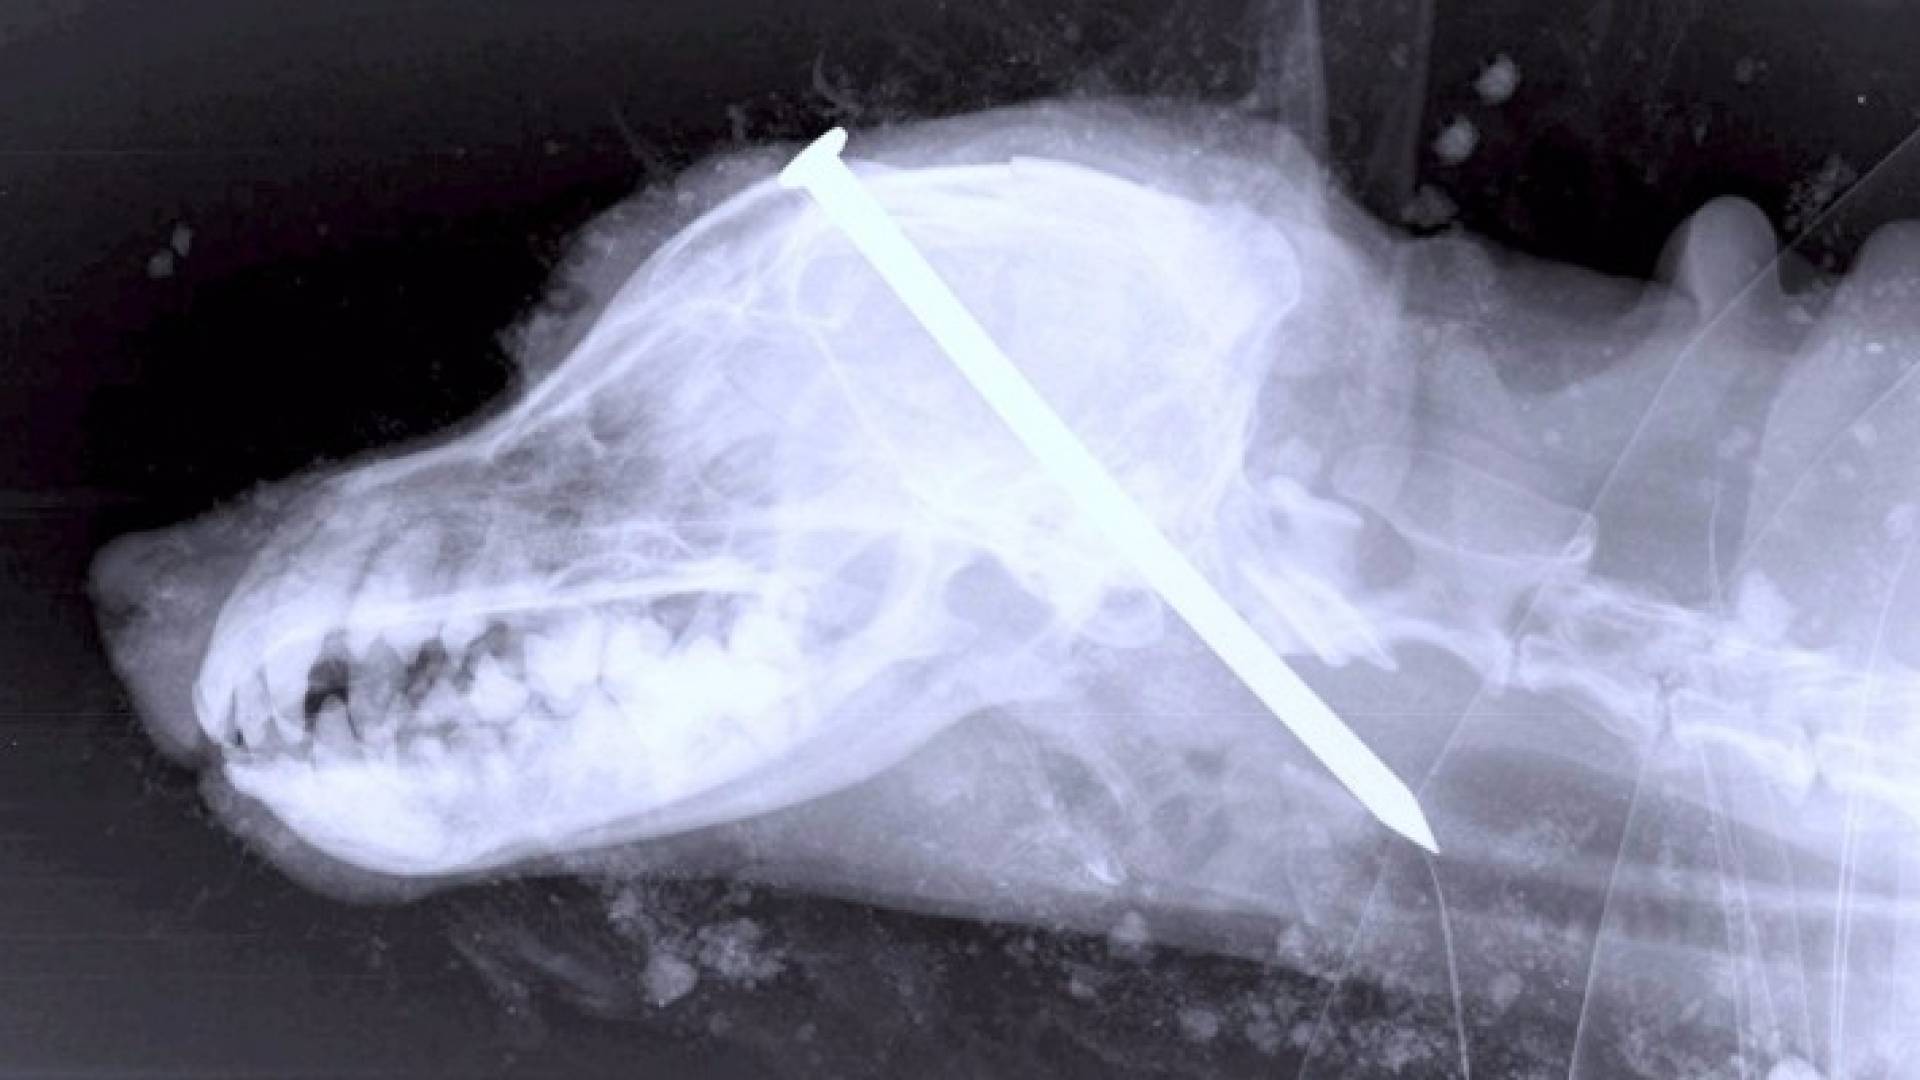

صدر حكم بـالسجن على رجلين بعد أن قاما بدق مسمار في رأس كلب صيد يدعى "النذل"، ودفنوه حيا، واصفين ما قاموا به بأنه "محاولة قتل رحيم فاشلة".

واكتشف شخصان آخران الكلب - وهو مكوم تحت التراب والخشب - أثناء سيرهما في غابة، وكان يعاني من إصابات بالغة جدا اقتربت به من الموت، فقاما بإبلاغ الشرطة ومن ثم نقله للعلاج.

وعثر الزوجان على الكلب بعد أن سمعا صوت نشيجه تحت كومة من التراب وري بها، لكن وضعه كان بائسا للغاية فهرعا به إلى العيادة البيطرية.